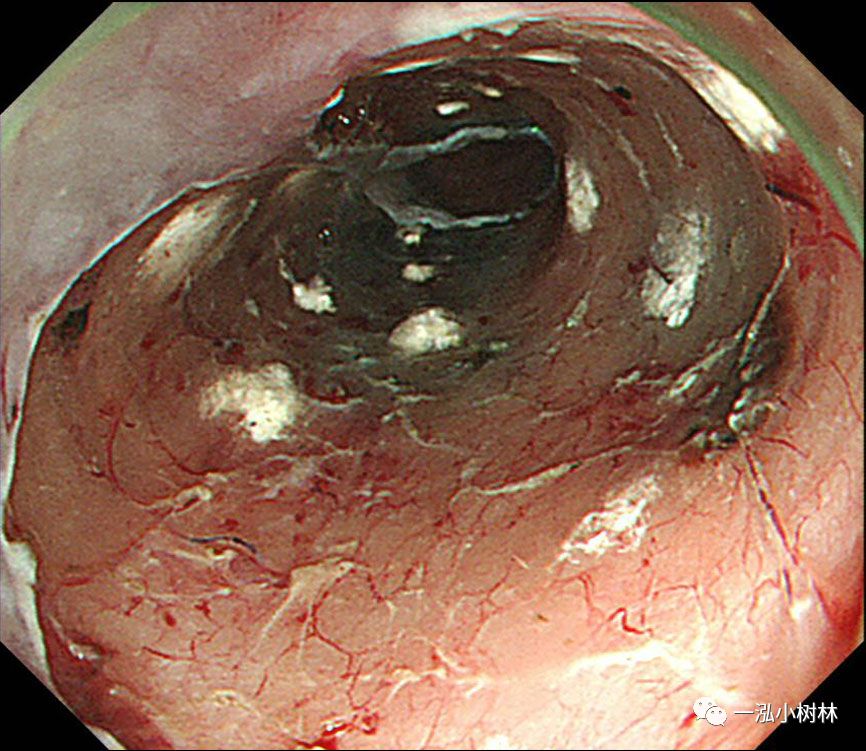

图12 在黏膜缺损处注射100mg曲安奈德预防食管ESD术后狭窄